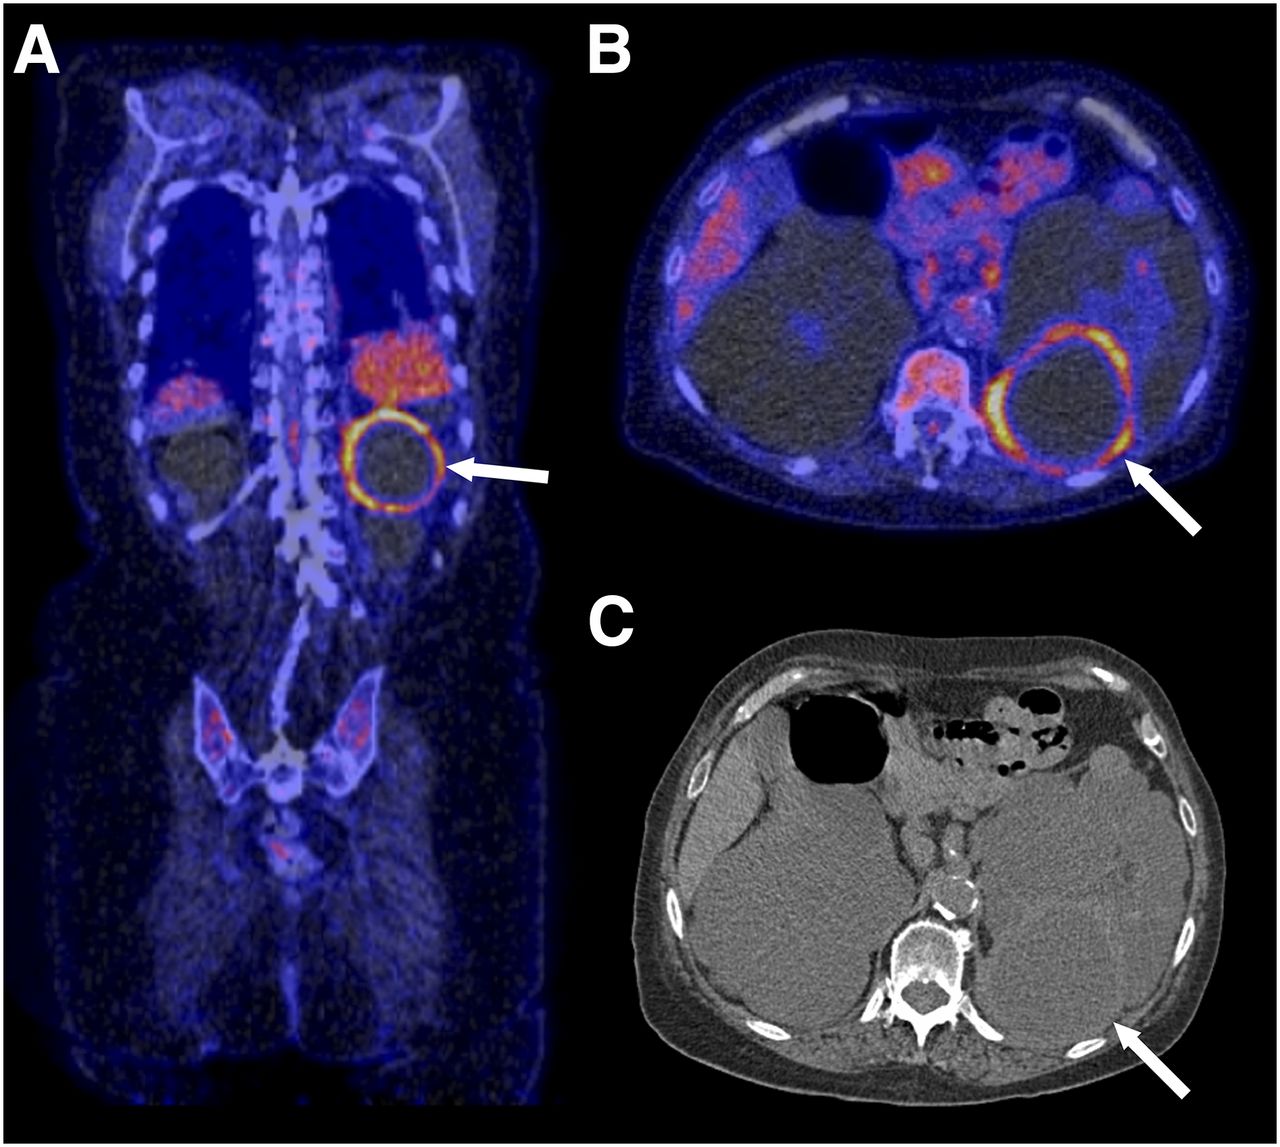

![2-[18F]FDG PET/CT parameters associated with WHO/ISUP grade in clear ...](https://www.researchgate.net/publication/343757008/figure/fig4/AS:941394646532127@1601457382875/The-axial-images-from-left-to-right-are-contrast-enhanced-CT-plain-CT-PET-and-PET-CT_Q320.jpg)